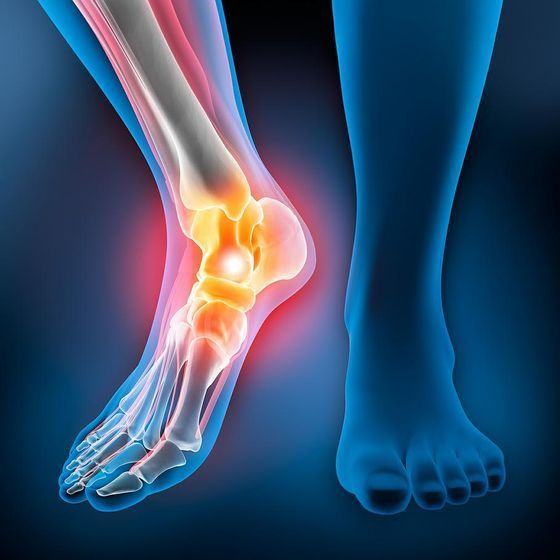

Les pathologies de la cheville:

Les entorses et instabilités:

Les entorses de la cheville, pathologie fréquente de la traumatologie du sport, doivent être traitées médicalement, en y associant de la physiothérapie. Si la cheville présente une instabilité récurrente, une chirurgie stabilisatrice peut être nécessaire par reconstruction ligamentaire.

Le but du traitement est de permettre un retour progressif à l’activité sportive.

Les douleurs au tendon d’Achille, c’est-à-dire sur la partie postérieure de la cheville, sont une maladie fréquente et nécessitent une prise en charge médicale, souvent de longue durée.

Cette pathologie peut aboutir à une rupture du tendon. La prise en charge comprend un traitement médical, associé à de la physiothérapie et plus ou moins des infiltrations. Si le tendon se déchire complètement, alors il est parfois nécessaire de le reconstruire chirurgicalement.

Les douleurs au talon:

Les douleurs au talon, ou talalgies, sont fréquentes et souvent dues à un disfonctionnement biomécanique du pied et de la cheville. Une prise en charge médicale et physiothérapeutique, plus ou moins associée à des infiltrations, permet de résoudre le problème